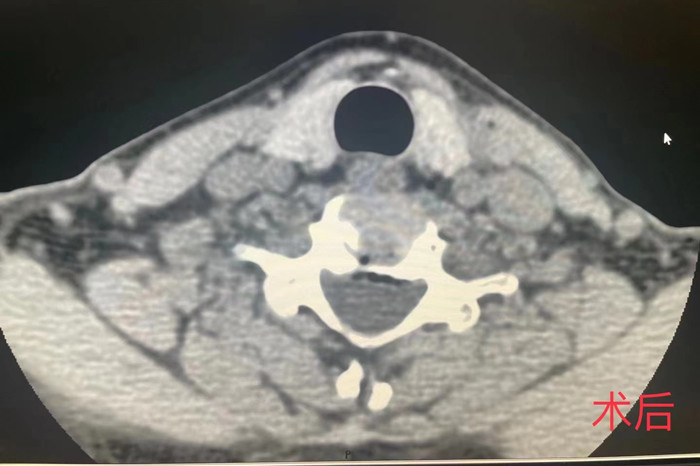

近日,我院疼痛科在南区影像科的配合下,成功开展了首例CT介导经皮穿刺颈椎间盘等离子射频髓核消融手术。

市民祁女士,今年51岁,近年来长期有头痛、颈肩部疼痛、僵硬和双上肢疼痛麻木不适等症状,辗转多家医院保守治疗均效果不佳,经我院疼痛科主任耿天勇对患者病史症状体征结合影像检查分析,诊断为颈椎间盘源性疼痛,遂决定在CT下为患者实施颈椎间盘射频消融的微创手术。

手术由安徽医科大学第一附属医院疼痛科主任王立奎和我院疼痛科副主任耿天勇共同主刀,在南区影像科医师的密切配合下,通过CT引导的精准定位,将细至0.9毫米的等离子射频针穿刺进入患者的病变椎间盘,成功对病灶部位进行射频消融,手术历时1小时左右。术后患者双上肢疼痛麻木即得到明显改善。